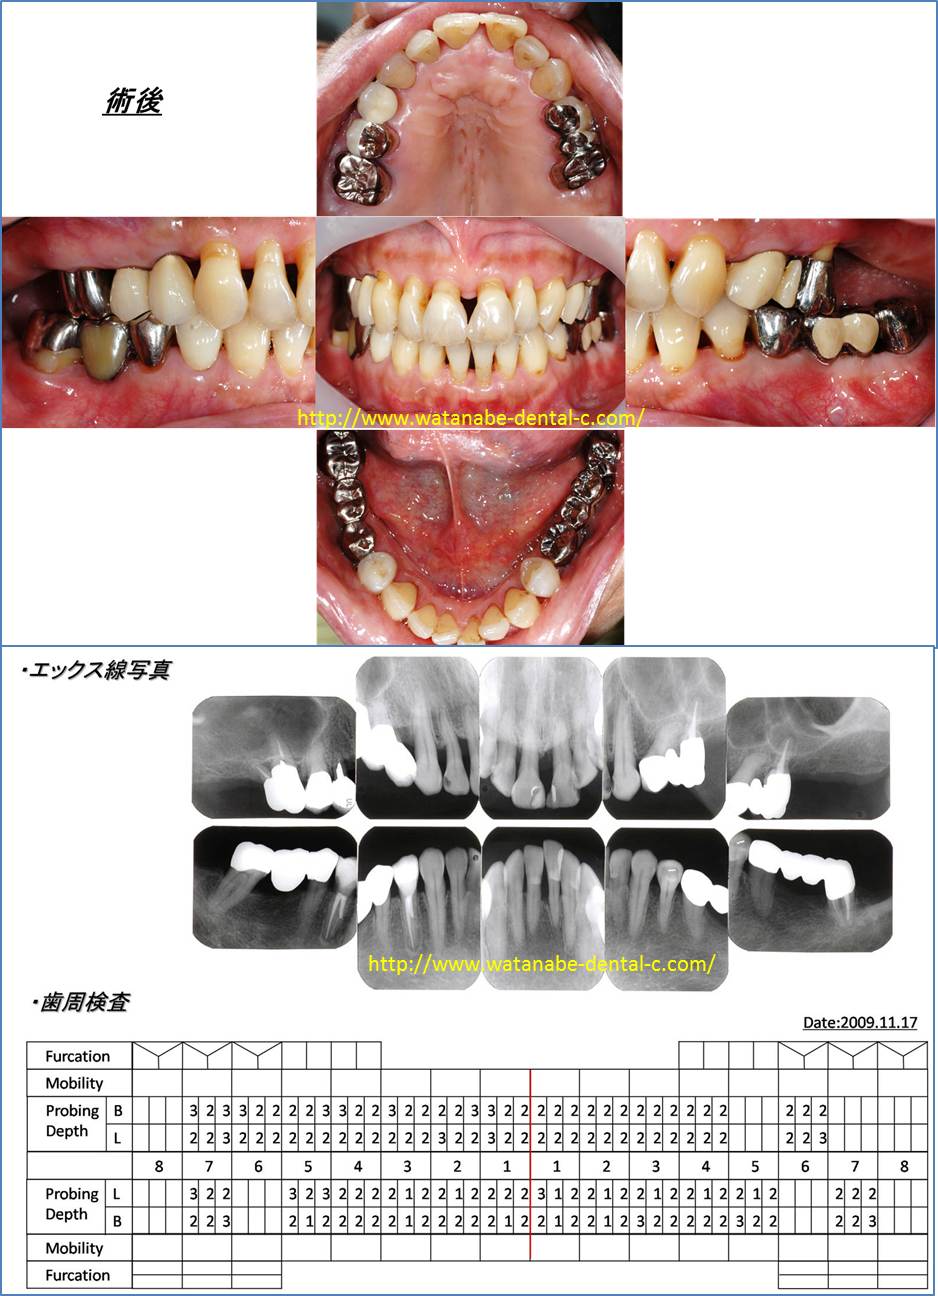

2.歯周病症例(主訴:前歯の開きが気になる。)

52歳女性、上の前歯が開いていることが気になり来院されました。前歯の間が開き、歯肉が腫れています。エックス線撮影、歯周ポケットの検査を行っています。全体的に5mm以上の歯周ポケットが認められます。このような場合、開いてしまった歯を削って冠を被せてしまえば、解決するのでしょうか?それでは解決しません。見た目の問題を解決しても、歯肉の中の根が汚染されていれば、冠を被せて一時的に見た目が回復しても、また開いてきてしまいます。そこで「治療計画」を立案します。ホームページでも示したように歯周病治療に限らず、歯科治療は「治療計画」がとても重要になります。その治療計画は「歯周病治療」をベースとしたものでなければならないと私は考えています。

まずは、歯周基本治療である炎症性因子のコントロールを行います。患者さんに1.歯間ブラシ、2.歯ブラシ、3.ワンタフトブラシにてブラッシング指導、スケーリング(歯石をとること)、スケーリング・ルートプレーニング(歯肉の中の根に付いている歯石をとり、汚染した根をきれいにすること)、不良な被せものを外して仮の歯の製作、左上の一番奥の歯は保存できないため抜歯。その後、再評価をします。歯周病治療では、この「再評価」がとても重要になります。「再評価」は、再度、歯周ポケット検査、歯の動揺、噛み合わせの確認を行います。この時点で歯周ポケットが改善されれば、歯周病治療は経過をみながら、被せものの治療へと移行します。しかしながら、特に奥歯に関しては歯周基本治療だけでは歯周ポケットは改善しにくいのです。「歯周基本治療」は「原因除去療法」といいます。歯の表面のプラークの除去、歯肉の中の歯肉縁下歯石の除去、無理な噛み合わせの調整により歯周病の原因および悪化させている原因を除去します。これで治れば一番良いのですが、まだ歯周ポケットが残っている場合は、「歯周外科処置」へ移行するのが望ましいです。この症例の場合、奥歯に関しましては歯肉剥離掻爬術を施行しました。

術後の写真と、歯周ポケット検査です。気になって来院された上の前歯の開きは改善しています。これは矯正治療を行ったわけではありません。上の前歯に関しては歯周外科処置も行っていません。患者さん自身の歯間ブラシ、歯ブラシ、ワンタフトブラシによるプラークの除去と来院されて行った「スケーリング・ルートプレーニング」により炎症を起こしていた因子が除去され、歯が自然と元の位置に戻りました。炎症は、歯をも動かしてしまうのです。炎症が改善すれば、歯の動揺が改善し、歯が自然と元の位置に戻ってくることがよくあります。歯周基本治療をきちんと行い、炎症を起こしている原因を除去することが最も重要になります。歯周ポケットも全体的に3mm以下に改善しました。